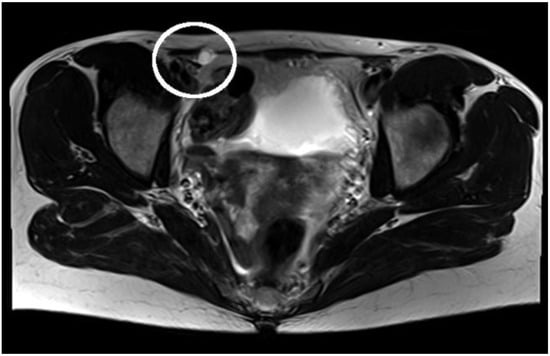

3. Case Report

| Cyst of the canal of Nuck | Cysts of the canal of Nuck present as an inguinal or genital, painless or painful swelling with no gastrointestinal symptoms. | On clinical examination, an inguinal or genital swelling is palpable. This mass shows no increase in volume by performing the Valsalva maneuver, and may is manually reducible. | On ultrasound, an anechoic or hypoechoic lesion without changes in the Valsalva maneuver and without vascular flow can be detected. Computed tomography (CT) imaging shows the cyst of the canal of Nuck as a homogeneous fluid-filled lesion along the round ligament. On magnetic resonance imaging (MRI), it shows as a thin-walled lesion, which appears hypointense on T1-weighted and hyperintense on T2-weighted sequences. |